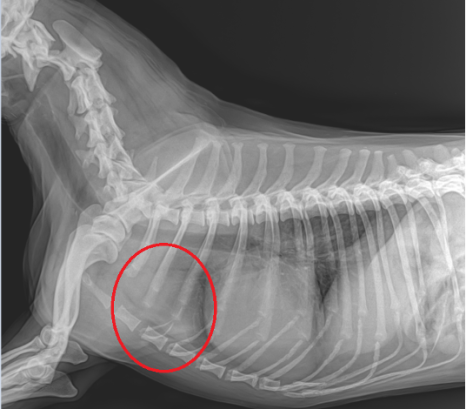

■ 흉부 방사선(X-Ray) 검사 결과

심장 크기의 변화나 폐수종 소견은 확인되지 않았으나, 심장 앞쪽 수준에서 종괴로 의심되는 소견이 발견되었습니다.

강아지 흉선 종양 방사선 (X-Ray)/ 기존 흉부 방사선 (좌) 증상 발생 후 흉부 방사선 (우) /출처: 에스동물메디컬센터 양산점

심장초음파 검사에서도 호흡 양상의 변화를 설명할 만한 심장성 원인은 확인되지 않아 CT 촬영을 통해 보다 정확한 평가를 진행하였습니다.